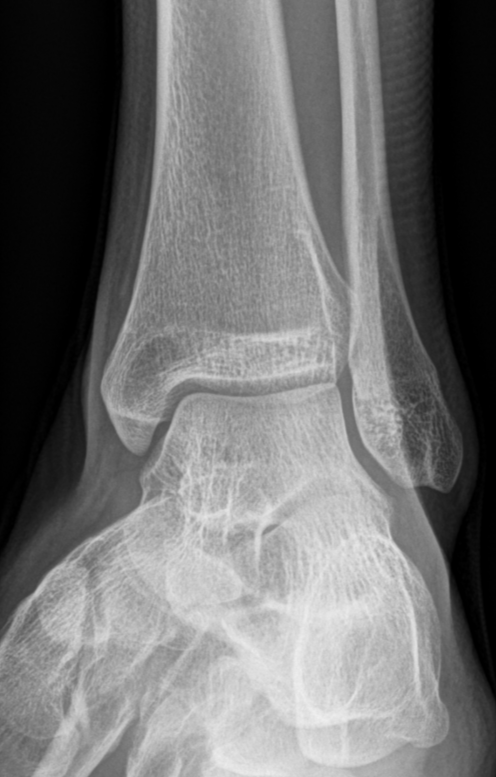

3. Mortise View of the Ankle